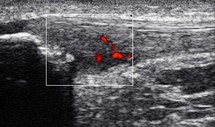

Cyril Fischhoff nous fait parvenir, depuis l’Ile Maurice, cette belle image caractéristique d’une enthésopathie proximale du ligament patellaire. Les lésions sont ici bien plus évoluées que celles décrites dans notre film intitulé « Jumper’s Knee ».

On observe :

- un aspect triangulaire du tendon rotulien à son enthèse sur la pointe de la rotule, avec une nette augmentation de son épaisseur dans l’axe antéro-postérieur.

- une zone hypoéchogène à la partie postérieure de l’enthèse de ce tendon, avec une disparition du classique aspect fibrillaire

- la présence d’un signal au doppler énergie témoignant d’un processus de néovascularisation au sein du tendon

- une calcification « dure » avec une ombre acoustique postérieure, à proximité de la pointe de la patella.